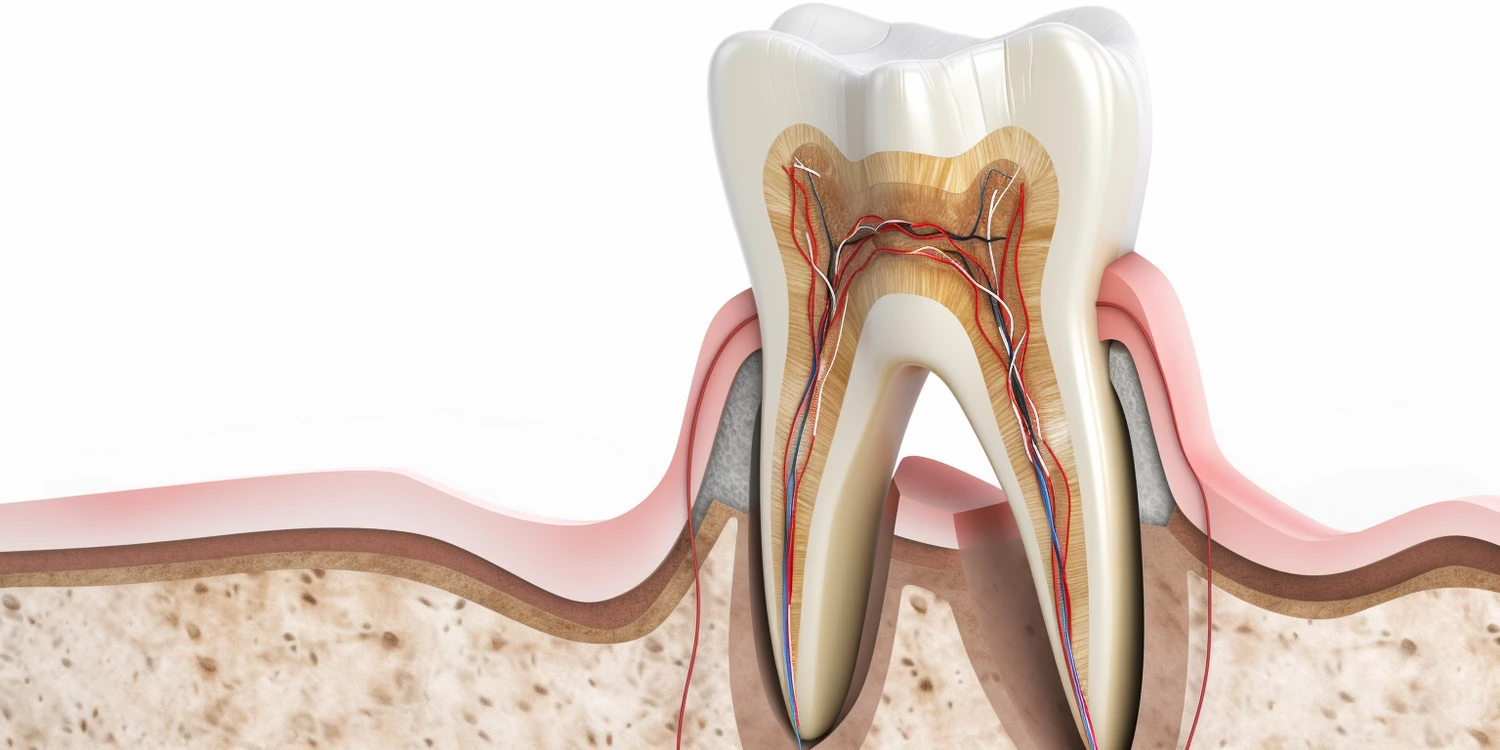

Leczenie kanałowe zęba to proces, który składa się z kilku kluczowych etapów, mających na celu usunięcie zakażonej lub uszkodzonej miazgi zęba. Pierwszym krokiem jest dokładna diagnoza, która zazwyczaj obejmuje wykonanie zdjęcia rentgenowskiego. Dzięki temu dentysta może ocenić stan zęba oraz zidentyfikować ewentualne problemy związane z korzeniami. Następnie przystępuje do znieczulenia pacjenta, co ma na celu zapewnienie komfortu podczas całego zabiegu. Po znieczuleniu dentysta wykonuje otwarcie zęba, aby uzyskać dostęp do komory miazgi oraz kanałów korzeniowych. Kolejnym krokiem jest usunięcie zakażonej miazgi przy pomocy specjalnych narzędzi endodontycznych. Po oczyszczeniu kanałów, dentysta dezynfekuje je, aby wyeliminować wszelkie bakterie. Na końcu kanały wypełnia się materiałem, który zapobiega dalszym zakażeniom oraz przywraca funkcjonalność zęba.